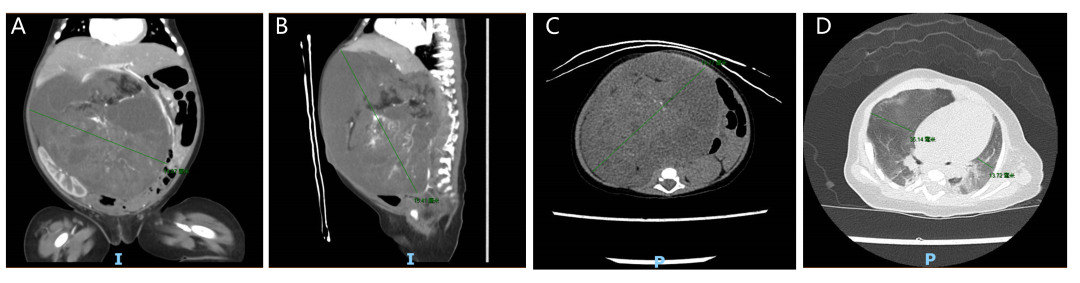

经过详细的体格检查和影像学评估,王德娟表示:“阳阳2月23天龄,但根据CT检查提示其腹腔内肿物尺寸已经增长到15.1cm×10.9cm×15.4cm(图1,A-C),腹腔内3/4都是肿瘤。阳阳6.5kg,肿瘤估计都有1.5kg。迅速增长的肿瘤不仅仅会影响他进食而延缓正常生长发育,还会压迫双侧肺脏及其他脏器,短时间内造成呼吸衰竭等恶果(图1,D),危害生命健康。目前肿瘤性质不明,我们需要采用多种手段进行肿瘤定位定性判断,尽早治疗。”

图说:图1 A-C,腹腔CT提示患儿腹腔内肿物尺寸为15.1cm×10.9cm×15.4cm;D,胸部CT提示患儿腹腔肿瘤压迫导致左侧胸廓减小,纵隔稍左偏。